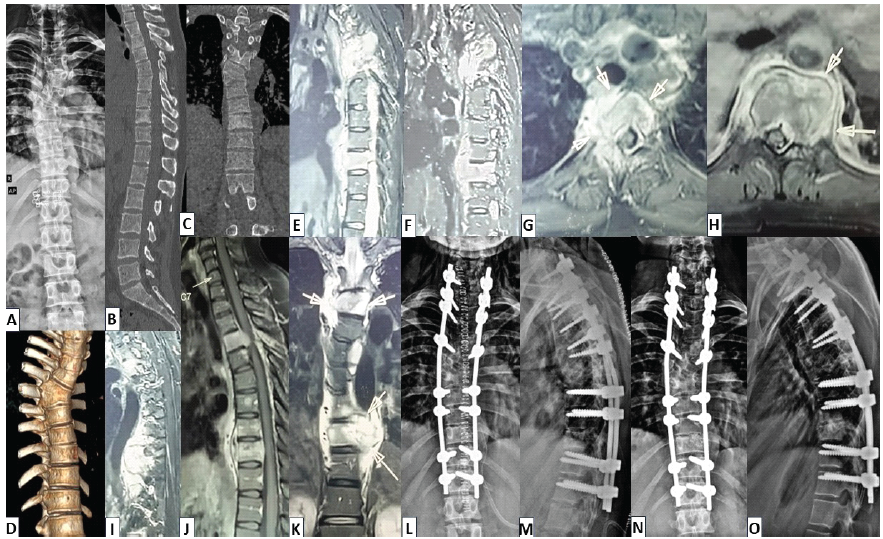

A 24-year-old male presented with persistent upper back pain for 3 months, constitutional symptoms (fever, loss of weight and appetite) for 1 month, progressive gait instability (bedridden for 1 week), and bladder involvement (48 h). He was already initiated on 1st line ATT (elsewhere) without histopathological confirmation. On examination, there was a palpable, tender gibbus at T6-T8, with frank upper motor neuron (UMN)-type neurological involvement (Frenkel-C). On imaging (plain radiographs, computed tomography [CT], magnetic resonance imaging [MRI]), a potential diagnosis of MSTB disease (non-contiguous; significant T7-T8 vertebral collapse, T11-T12 disease, left L2 disease, L5-S1 left pedicle/vertebral disease, significant epidural collection/granulation tissue at T7-T8 and T10-T12) was made (although aggressive neoplastic lesions like lymphoma were also considered; Fig. 1a-k).

Figure 1: (a and b) Case 1 – Radiological findings pre-operative X-rays: Antero-posterior (AP) and lateral views of thoracolumbar spine showing increased haziness and collapse of T7, T8 vertebrae, (c) Lateral view of lumbar spine showing lytic lesions in the vertebral bodies of T11, T12, L2, (d and e) Mid-sagittal computed tomography (CT) sections showing complete collapse of T7, T8 vertebrae with focal kyphosis around 20°, (f and g) Para-sagittal CT sections showing multi-level lytic lesions at T7, T8, T11, T12, L2, L5, (h) mid-sagittal sequence of contrast-enhanced magnetic resonance imaging (CE-MRI) image showing hyperintense signals in pre-vertebral and epidural regions suspicious for granulation tissue with T7 collapse and T11, T12, L2 hyperintense areas with preserved vertebral height, (i) axial section of CE-MRI showing abscess within left vertebral body and pedicle of sacrum, (j) coronal section of CE-MRI showing bilateral para-vertebral abscess and granulation tissues at T7-8 level, (k) sagittal section of CE-MRI showing complete destruction of T7-T8 vertebrae with paravertebral abscess at T12 level, (l and m) intra-operative images showing decompression of the thecal sac, anterior cage reconstruction and posterior instrumentation, (n and o) immediate post-operative AP and lateral radiographs showing long-segment posterior instrumentation and cage construct, (p and q) follow-up radiographs at 3 months showing good implant position and healing, (r and s) follow-up radiographs at 12 months showing good bony fusion at T7,T8 levels and satisfactory healing.

In view of worsening neurodeficit, the decision to go ahead with immediate surgical intervention (without prior biopsy) was made. The surgical steps included T4-L3 posterior instrumented fusion, laminectomy between T7 and T12, T7/T8 corpectomies, and debridement of unhealthy granulation tissues. L5-S1 lesion was managed conservatively at this point, with a potential plan of distal extension (in case of additional deterioration; Fig. 1 l and m).The histopathological examination (HPE) report was suggestive of tubercular infection (with granuloma). Gene Expert and tubercular culture were negative. He was started on ATT (1st line) based on the HPE and clinico-radiological presentation. At 6 weeks, barring some residual UMN findings, his neurological status had almost completely recovered. He responded well to ATT clinically, and his inflammatory markers also gradually improved. At 9 months, MRI revealed complete resolution of all lesions. ATT was discontinued at the end of 10 months (Fig. 1n-s). Patient is clinically stable with 18 months of follow-up.